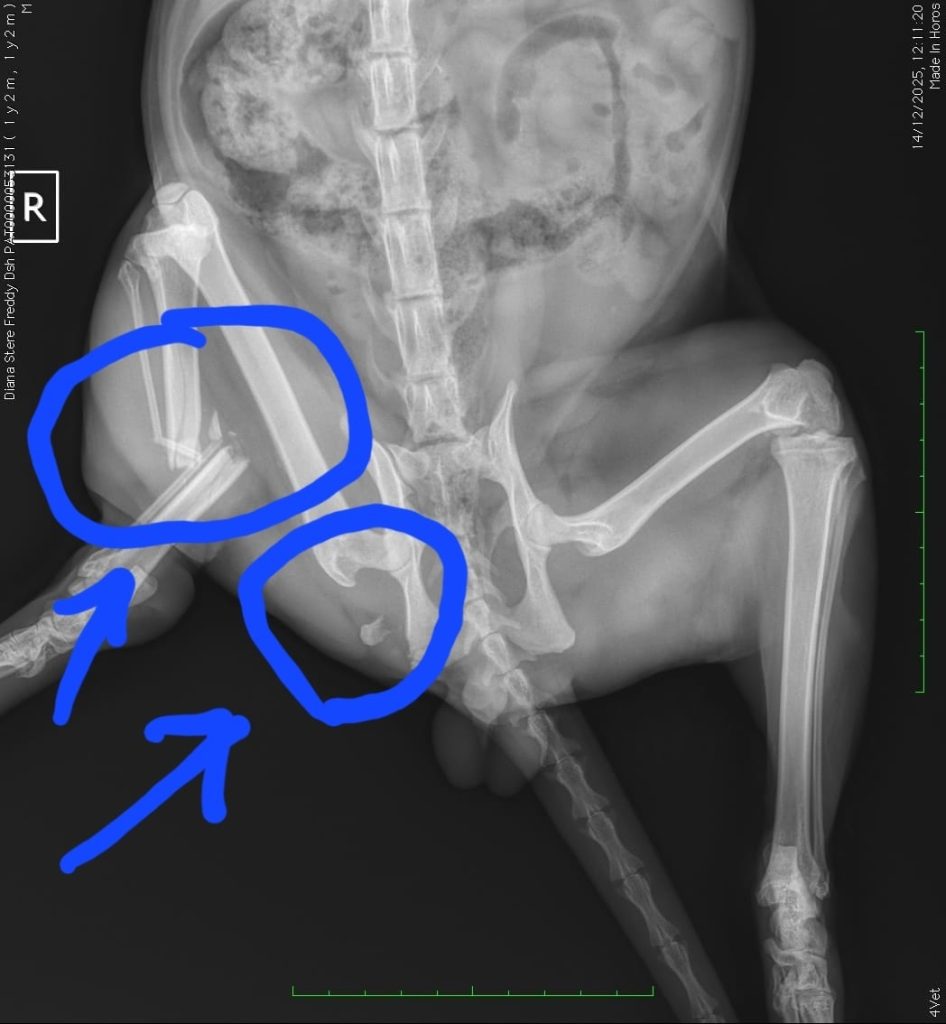

V-am încercuit în fotografii fracturile, arată foarte rău și trebuie intervenit cât mai repede.

“Freddy este un motanel de un an si 3 luni si face parte dintr-o colonie de pisici ce traiesc intr-o gradina. Este hranit si ingrijit, insa viata pe strada este plina de pericole, asa ca intr-o zi Freddy a plecat din gradina si nu s-a mai intors pret de 10 zile. L-am cautat peste tot in zadar. Intr-o dimineata cand piedusem speranta ca mai traieste, s-a intors singurel, schiopatand cu piciorusul din dreapta spate… Astazi am fost cu el la radiografii. Are piciorul rupt si bazinul afectat. Fara operatie, Freddy nu doar ca o sa traiasca cu niste dureri ingrozitoare, dar are viata pusa in pericol, fiind predispus la infectii. Este un pisoi tanar, extrem de bland si cuminte.